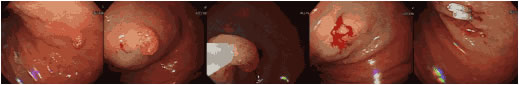

염증성 용종이나 과증식성 용종의 경우 암으로 발전할 가능성이 거의 없다고 알려져 있습니다. 전체적으로 보아 약 0.1% 정도에서 암이 발견되거나 암으로 발전합니다. 염증성 용종이나 과증식성 용종의 경우에는 일반적으로 제거를 강력히 권유하지는 않습니다만 크기가 큰 경우에는 내시경을 이용하여 제거하는 것이 바람직합니다. 대부분은 내시경적으로 제거할 수 있고 이를 내시경적 용종 절제술이라고 합니다. 이는 내시경을 위 속에 넣은 후에 전기 올가미로 집어 올려 잘라내는 방법입니다. 이 방법은 매우 간편하고, 개복 수술에 따르는 위험이 없기 때문에 안전하게 시술할 수 있습니다.

위암의 근본적인 예방이 현실적으로 불가능한 현재로서는 위암을 조기 진단하여 제거하는 것만이 최선의 치료 방법입니다. 조기위암 중 크기가 작고(융기형의 경우 2cm이하, 함몰형의 경우 1cm이하), 암이 점막 층에 국한되어 있는 경우에는 내시경만으로도 완치를 기대할 수 있습니다.